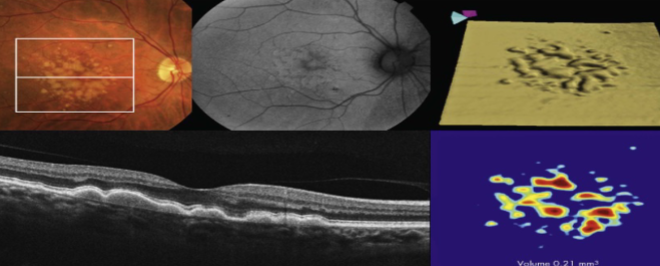

type 1 MNV

fibrovascular PED

late leakage from undetermined source (poorly defined neovascularization)

speckled hyperfluorescence

dye pooling late in study

poorly defined

PCV

similar to type 1 MNV w/ dilated vascular elements (polyps)

MNV type 1

MNV type 1

MNV type 1

MNV type 1

MNV type 1